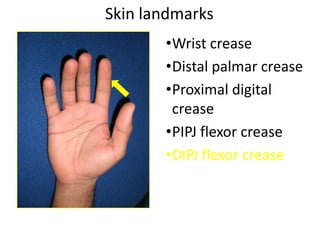

- Naming the bones, joints, tendons, nerves and skin landmarks of the hand and wrist.